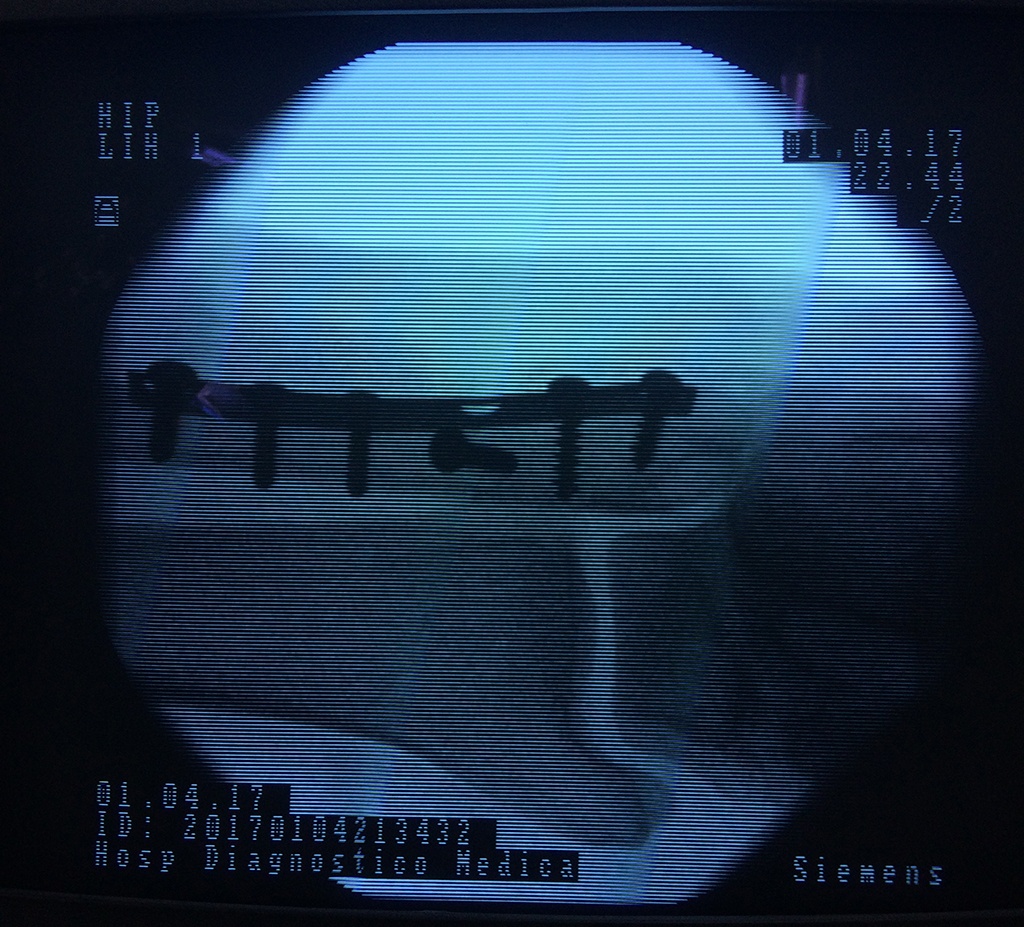

Cirugías de Cadera